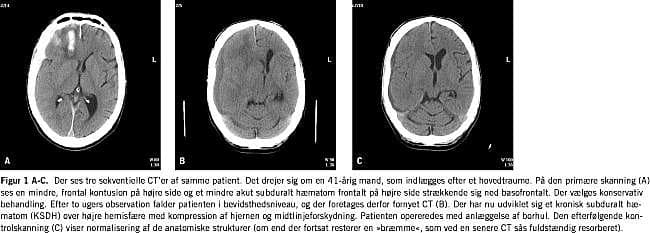

Efterhånden som KSDH modnes, skifter dets CT-udseende fra hyperdenst (frisk blod/koagler) til isodenst og derefter til hypodenst [14], en proces som tager 2-4 uger (Figur 1 ). Akut blødning i det eksisterende hæmatom fører til et CT-udseende med vekslende hypodense og hyperdense områder [8, 15]. Hyperdensitet i hæmatomkaviteten er udtryk for frisk blod med dannelse af koagler. Iso- og hypodense hæmatomer er i reglen helt flydende uden koageldannelse.